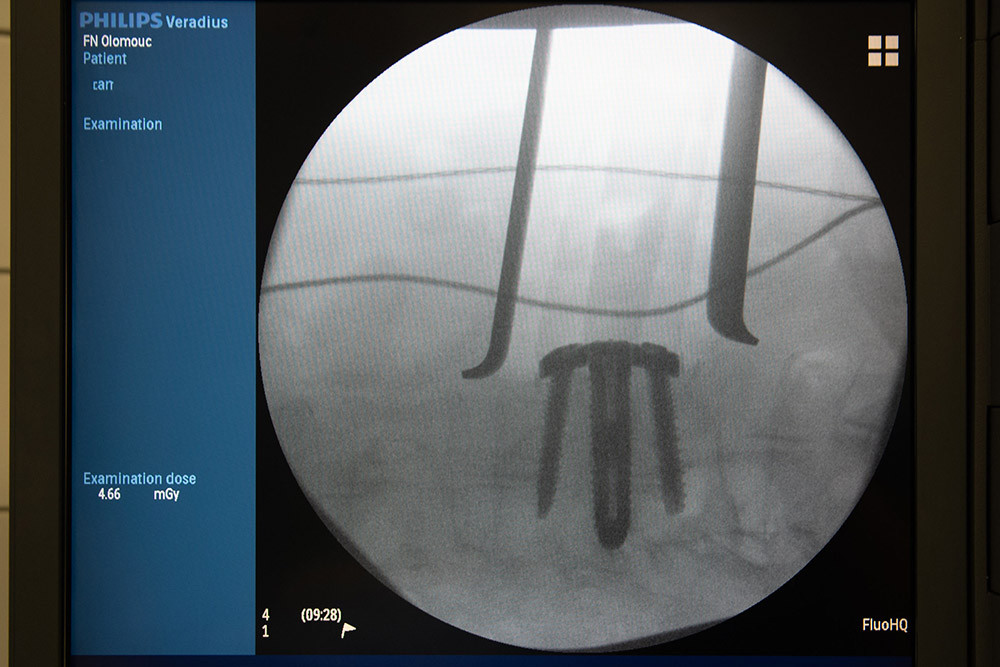

Titan, vanad a hliník: jedinečný meziobratlový implantát z Olomouce pomáhá pacientům už pět let